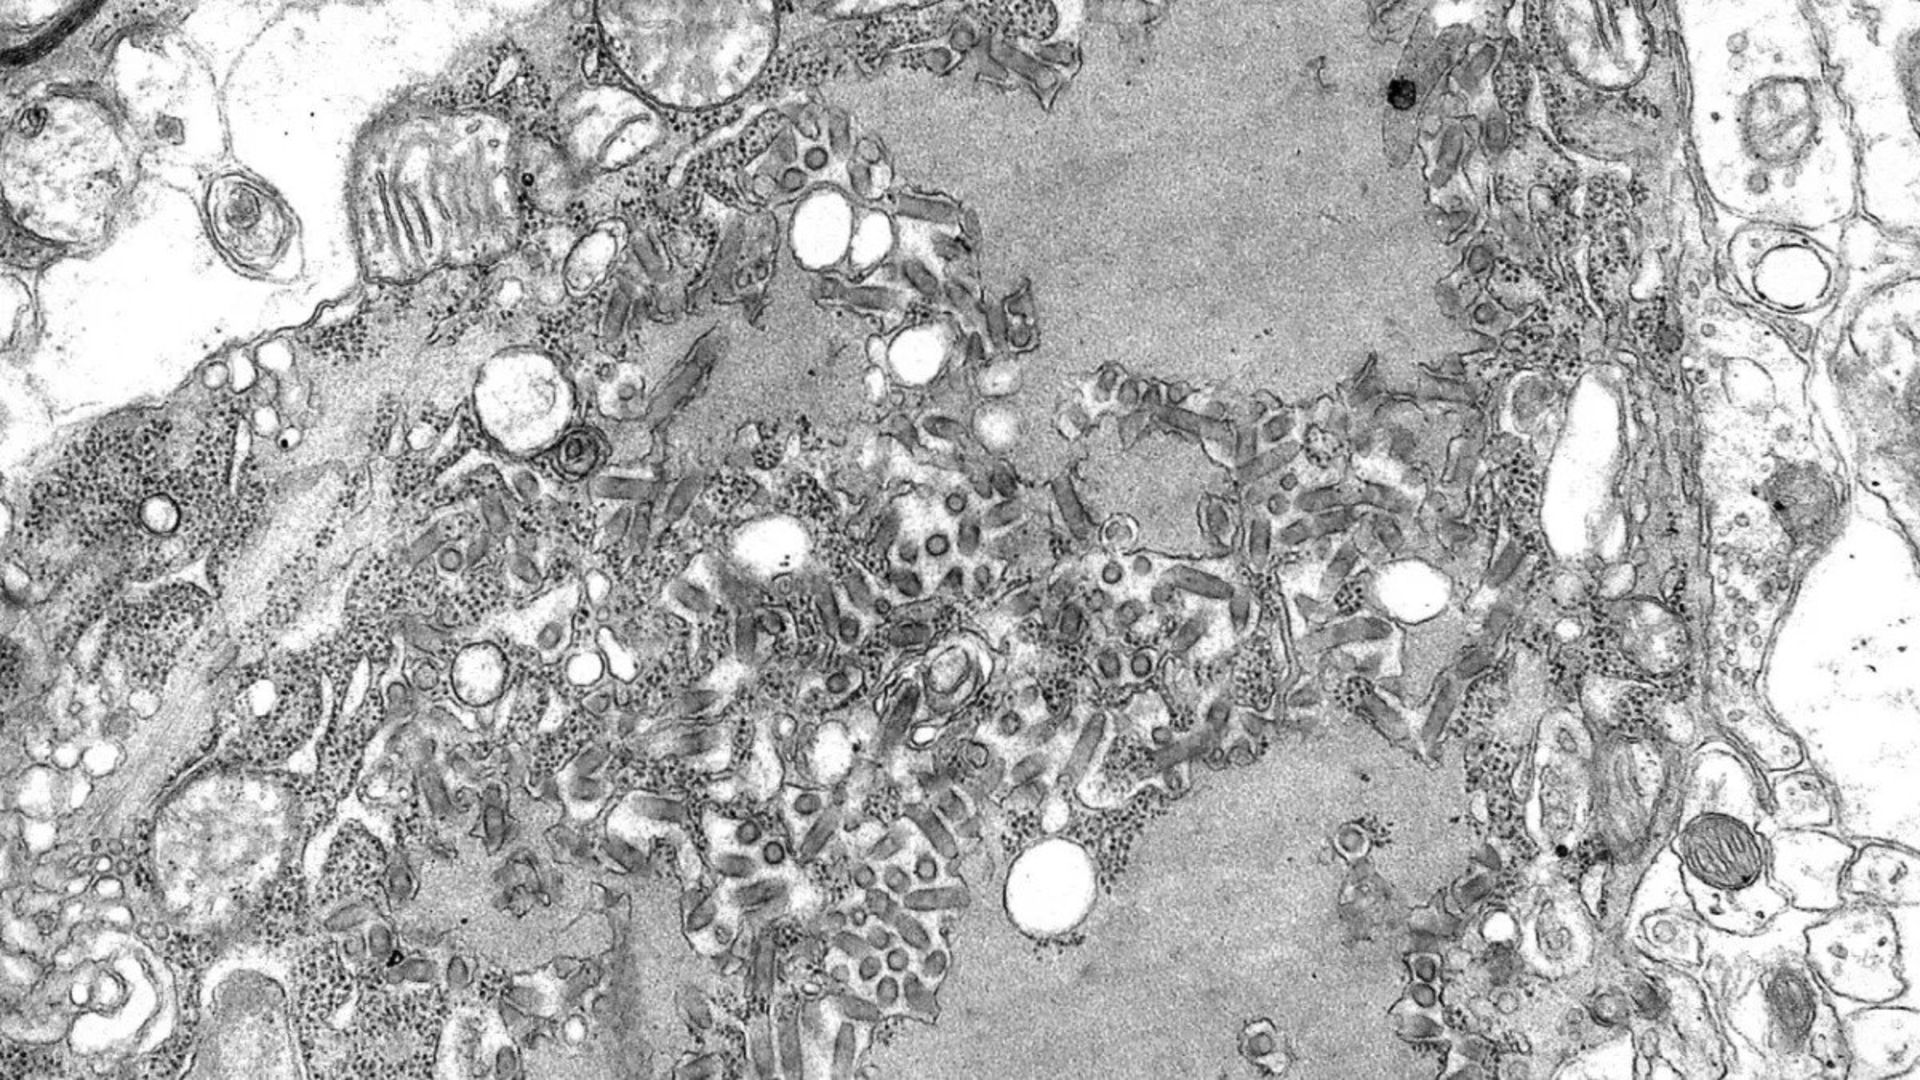

این تصویر ویروس هاری که با میکروسکوپ الکترونی گرفته شده است، ذرات ویروس را نشان می‌دهد.

عفونت ناشی از این ویروس بر اثر گزیدگی یا ایجاد خراش از سوی یک پستاندار آلوده رخ می‌دهد. وقتی شخصی دچار گزیدگی می‌شود باید بلافاصله واکسن هاری دریافت کند یا از پخش شدن بیشتر بیماری جلوگیری کند. در غیر این صورت ویروس به مغز و اعصاب آسیب می‌رساند. مرگ به دنبال بروز علائم رخ خواهد داد. نرخ مرگ و میر ویروس هاری ۹۹ درصد است.